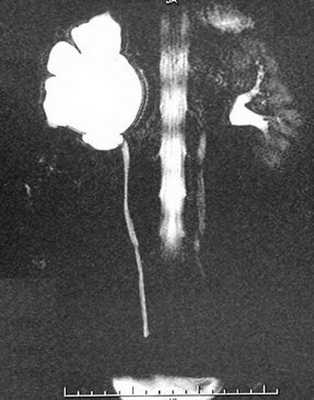

Рентгенологические методы обследования

Если нет противопоказаний, то рентгенологические исследования с контрастом являются приоритетными в диагностике гидронефроза.

Экскреторная урограмма. Стеноз лоаночно-мочеточникового сегмента, гидронефроз справа.

Благодаря рентгеноконтрастным препаратам метод дает оценку экскреторным функциям почек. Он эффективен на начальных стадиях заболевания, по мере нарастания патологии диагностическая эффективность снижается.